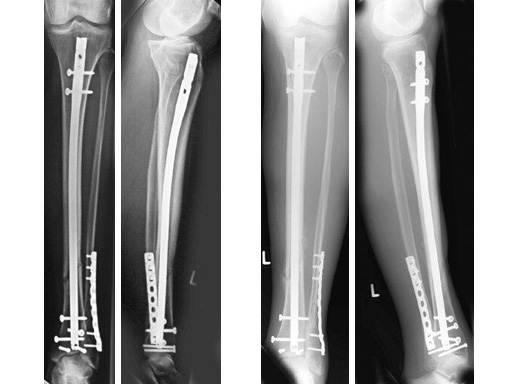

Type III open distal tibial fracture with beginning compartment syndrom following a traffic accident.